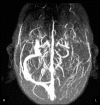

Although catatonia is a well-known psychiatric syndrome, there are many possible systemic and neurological etiologies. The aim of this case report was to present a case of a patient with cerebral venous sinus thrombosis and infarction in which catatonia was the clinical manifestation of a possible nonconvulsive status epilepticus. To our knowledge, only one such case has been reported in the literature, which had a simplified diagnostic investigation. It is important to correctly recognize the organic cause underlying catatonia in order to treat the patient as soon as possible thereby improving outcome. Therefore, physicians need to update their knowledge on catatonia, recognizing that it can be part of a psychiatric or neurologic condition.